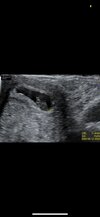

Co do usg to po skonczonym 6 tygodniu (czyli 6 tydzien i 1 dzien i pozniej) powinno juz byc serduszko. Im pozniej, tym pewniejsze. Czyli tak, jak dziewczyny pisaly, 7 tydzien (6+ liczy sie jako siodmy tydzien).